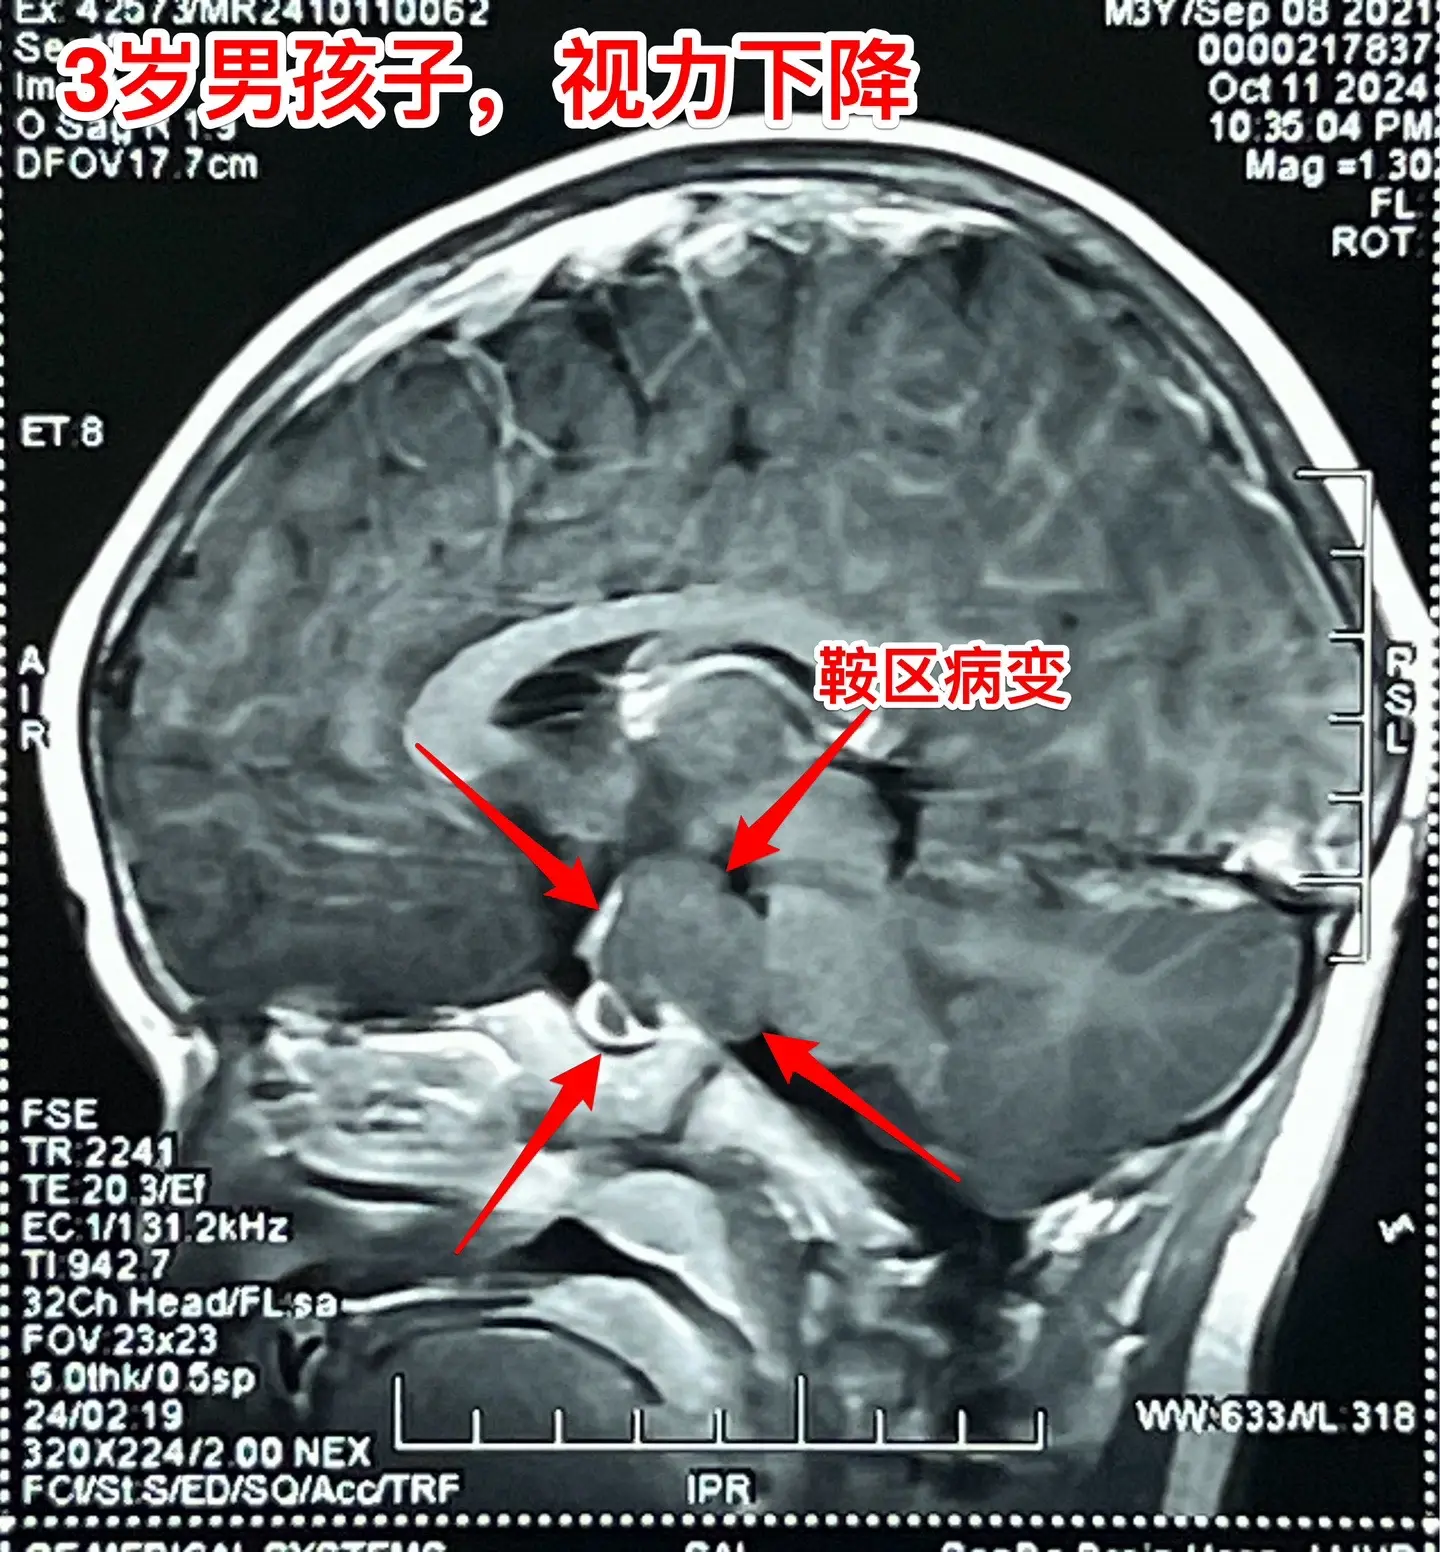

鞍区高密度囊肿-高密度不等于钙化。拉克氏囊肿在CT扫描中大多数呈低密度影,少数呈现比较均匀的高密度影,但是绝对不是钙化。不能误认为是颅咽管瘤。 三岁男孩子因偶然原因行CT扫描发现鞍区病变。测视力才发现患儿的视力有下降(0.3)。根据CT、磁共振可以判断这是拉克氏囊肿,病变没有钙化。 拉克氏囊肿如果压迫视神经、视交叉造成视力下降或者视野缺损,则有手术指征。 今日10.25经翼点入路将病变切除。术中快速冰冻报告为拉克氏囊肿。